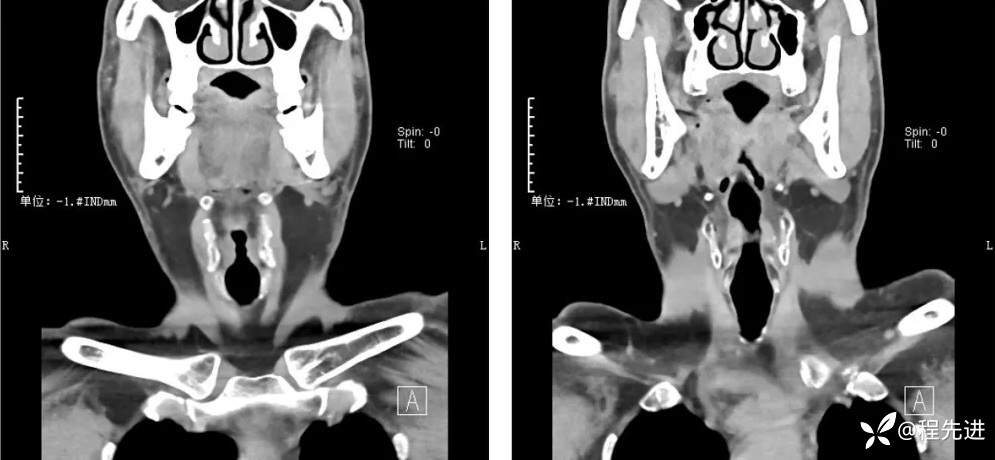

CT检查: